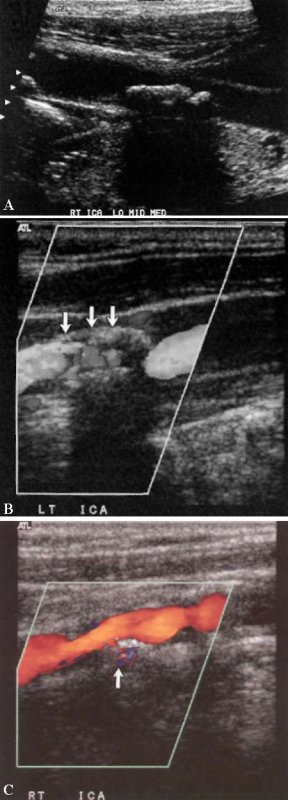

Язва бляшки представляет собой дефект или полость, размеры которой более 2×2 мм. Изъязвленная бляшка на ангиографии представляет собой важный прогностический признак высокого риска цереброваскулярных осложнений. Ангиография и УЗИ обладают низкой чувствительностью и низкой специфичностью при диагностике изъязвленных бляшек. Цветовая допплерография позволяет обнаружить область обратного кровотока в пределах изъязвленной бляшки (фото 9).

Фото 9. Атеросклеротическая бляшка в сонной артерии. А – кальцинированная бляшка с акустическим затенением. В – стрелкой обозначена некальцинированная (мягкая) бляшка. С – изъязвленная бляшка: стрелкой обозначен поток внутри бляшки